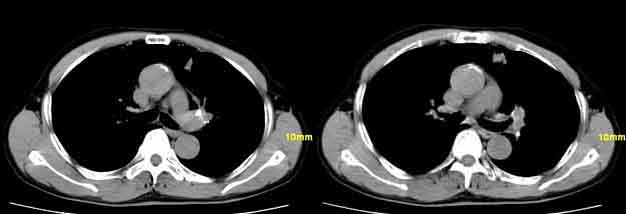

因为;纵隔窗内见钙化影,病灶呈条索样,并且病人反复咳血,所以考虑结核。